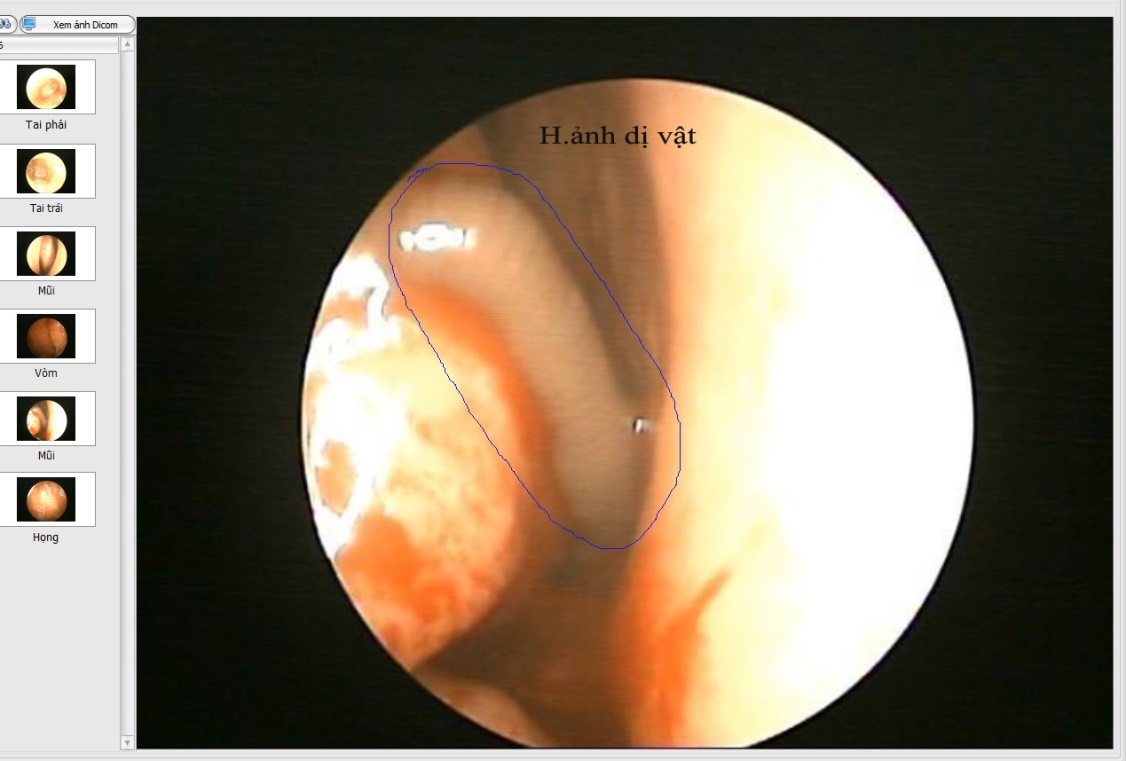

Dị vật sống trong mũi phải bệnh nhân sau khi được lấy ra

Hình ảnh nội soi